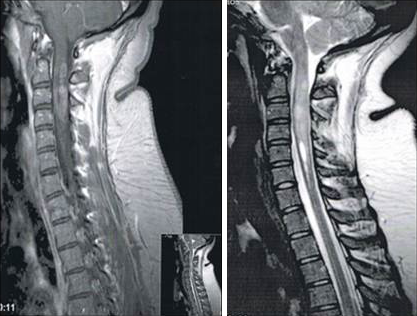

The patient performed in the emergency room a CT and blood tests. On the same day she was admitted to the Neurology Department where she performed MRI (Figure 2 [Fig. 2], Figure 3 [Fig. 3]), lumbar punction with analysis of CSF. More specific tests and chest CT for screening of thymoma were requested. On the next day our patient was seen at the Ophthalmology Department where she made the following imaging tests: optical coherence tomography, angiography, visual fields and electrophysiological tests.

Figure 3: Sagittal T2 weighted MRI of spinal cord showing swelling of the cervical segments (more than 3 contiguous segments) with high signal intensity.